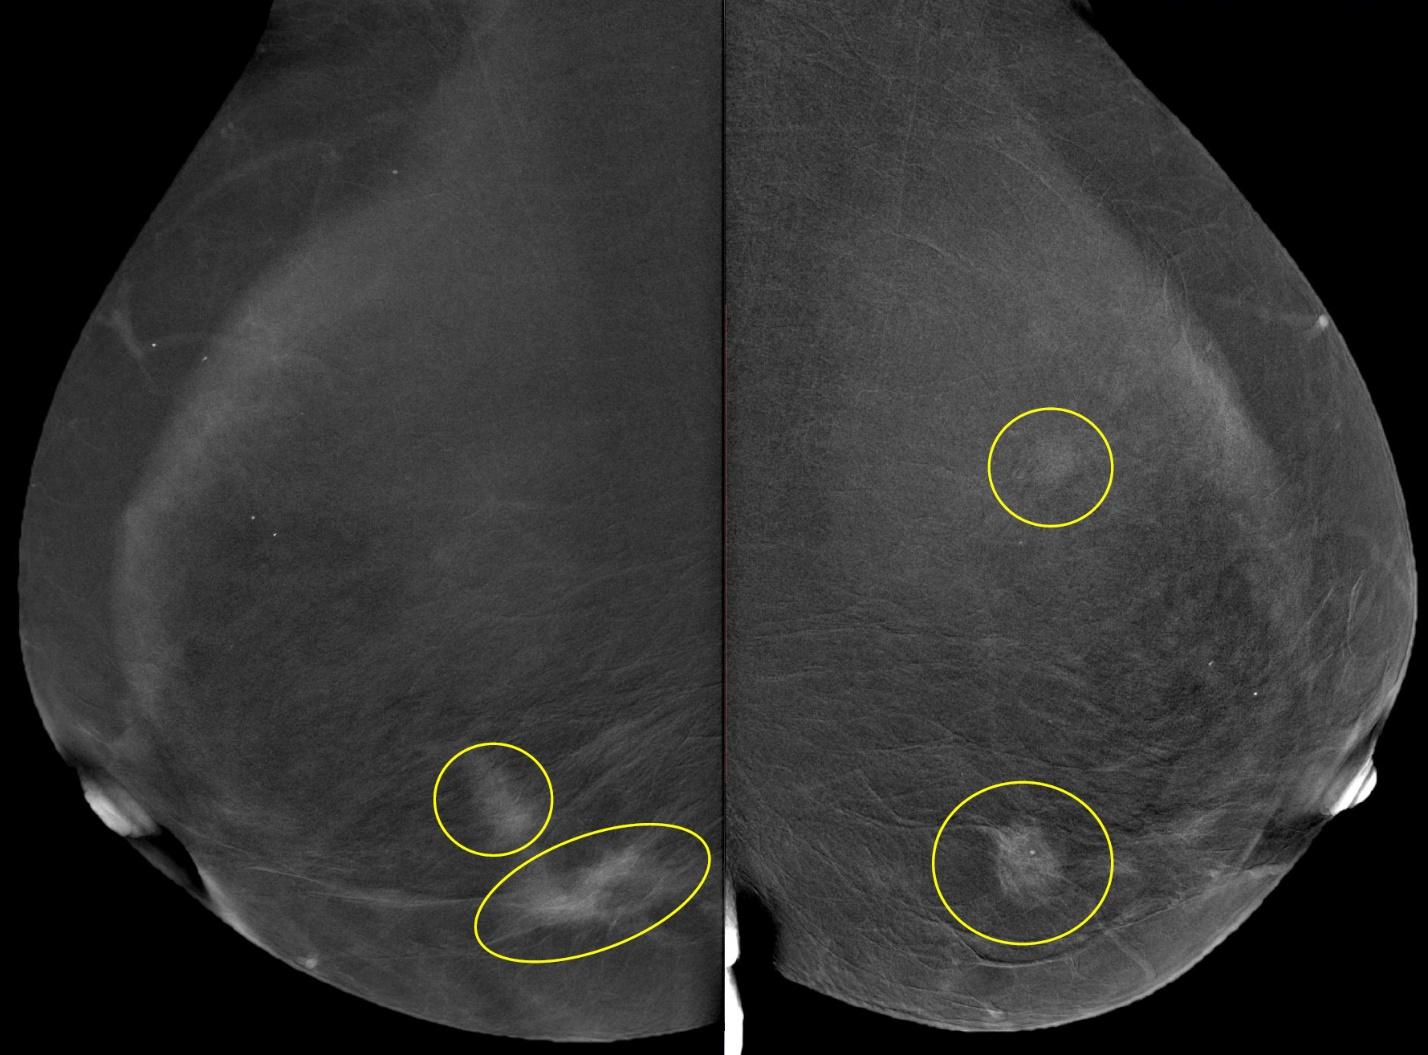

Пример сравнения классической маммограммы и томосинтезного среза

FFDM (2D) / BTM (3D)

Цифровой томосинтез, или 3D маммография, часто используется вместе с классической 2D маммографией для обследования плотных молочных желез или в качестве дополнительного метода при обнаружении патологий. Основным показанием для выполнения 3D маммографии является высокая плотность молочных желез (ACR C и D). В таких случаях может быть проведена маммография как в 2D, так и в 3D режимах в качестве основного метода обследования для пациентов старше 40 лет. В редких случаях томосинтез может быть использован после маммографии у женщин с низкой плотностью молочных желез для дополнительной диагностики, например, при подозрении на опухоль в молочной железе.

Сравнение томосинтезных срезов, сделанных на разных маммографических аппаратах

Методика CESM в тезисах

- Получение двух снимков с разными режимами экспонирования: один снимок «мягкий», значение анодного напряжения находится в диапазоне от 26 до 32 кВ, второй - «жесткий», анодное напряжение устанавливается в пределах от 40 до 49 кВ.

- Снимки делаются после введения пациенту йодсодержащего контрастного вещества внутривенно.

- Снимки выполняют следом друг за другом в течение короткого промежутка времени при одинаковой компрессии молочной железы.

- Далее производится комбинация изображений таким образом, чтобы интенсивность тени в каждой точке снимка была пропорциональна концентрации контраста в соответствующем участке молочной железы.

Шаг 1. Получение низкоэнергетического «мягкого» изображения с использованием стандартных доз, применяемых в маммографах.

Шаг 2. Получение высокоэнергетического «жесткого» изображения с использованием среднего значения мощности излучения.

Шаг 3. Сравнение и вычитание двух изображений, сигнал от фоновой ткани молочной железы подавлен, структуры с контрастным веществом хорошо видны на снимке.

Клинические примеры применения CESM